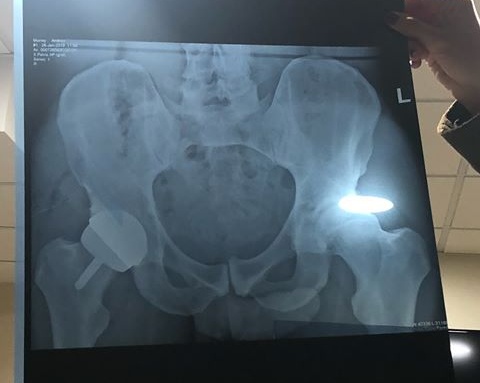

Putting up a photo of himself and the result of his hip scan, he said he feels a bit better now and although bruised, he is happy it was successful and hopefully that will be the end of his hip problem.

“I now have a metal hip,” Murray said in his social media post following his operation. “Feeling a bit battered and bruised just now but hopefully that will be the end of my hip pain. He said:

“I underwent a hip resurfacing surgery in London yesterday morning…feeling a bit battered and bruised just now but hopefully that will be the end of my hip pain I now have a metal hip as you can see in the 2nd photo and I look like I’ve got a bit of a gut in photo 1”